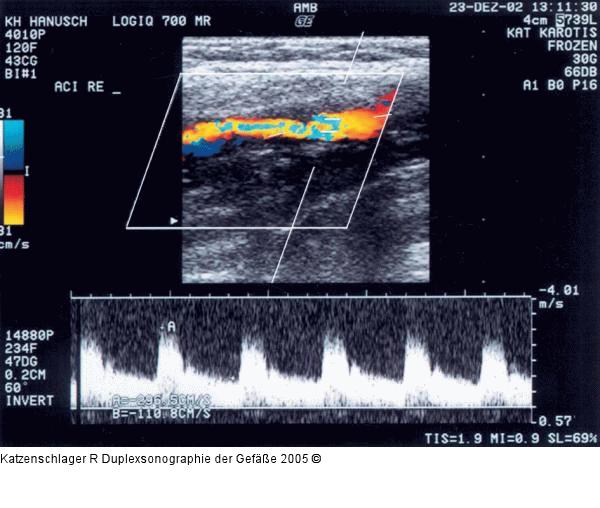

Abbildung 7c: Duplexsonographie - Karotis

Hochgradige > 70 % ACI-Stenose rechts (Vmax 2,9/1,1 m/sec) |